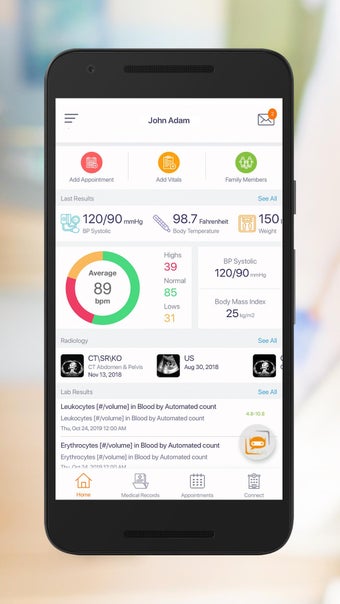

Carepassport là một ứng dụng Android cung cấp cho bệnh nhân một giải pháp toàn diện để quản lý dữ liệu y tế của họ. Ứng dụng cho phép bệnh nhân truy cập và lưu trữ an toàn dữ liệu y tế của mình, lên lịch hẹn, xem hình ảnh y tế, báo cáo xét nghiệm và lâm sàng từ các nhà cung cấp khác nhau, và chia sẻ chúng bằng công nghệ tính toán di động tiên tiến. Với Carepassport, bệnh nhân có thể dễ dàng quản lý nhu cầu chăm sóc sức khỏe của mình chỉ với vài lần chạm trên thiết bị di động của họ.

Một trong những tính năng quan trọng nhất của ứng dụng là việc truy cập dữ liệu y tế một chạm dễ dàng. Bệnh nhân có thể truy cập dữ liệu y tế của mình hoặc dữ liệu đại diện gia đình một cách an toàn và nhanh chóng, làm cho nó trở thành một công cụ tuyệt vời để quản lý lịch sử bệnh án của họ. Ứng dụng cũng cho phép người dùng tìm kiếm các phòng khám và bệnh viện gần đó, lên lịch hẹn, và thậm chí nhận chỉ đường đến cuộc hẹn của họ qua Uber. Ngoài ra, bệnh nhân có thể giao tiếp với nhà cung cấp chăm sóc của họ qua tin nhắn an toàn, chia sẻ hình ảnh y tế và cho phép thành viên gia đình truy cập dữ liệu y tế của họ thông qua cài đặt proxy an toàn. Cuối cùng, ứng dụng cung cấp tài liệu giáo dục liên quan đến chăm sóc sức khỏe và có thể kết nối với các thiết bị đeo được hoặc nhập dữ liệu y tế thủ công.